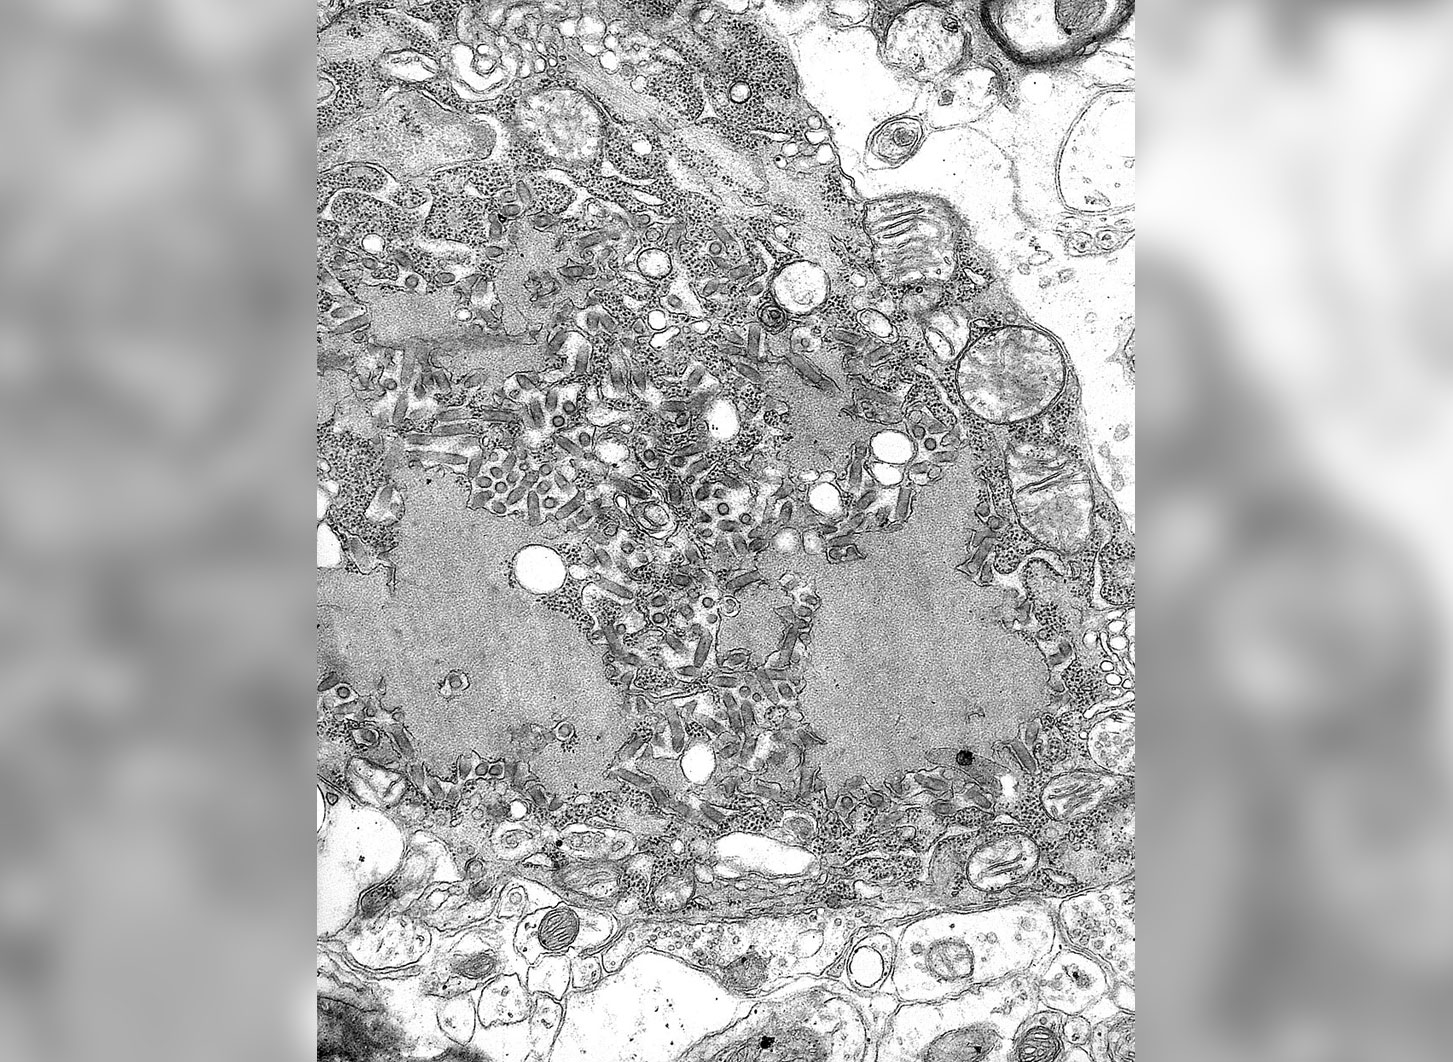

Вирус бешенства под электронным микроскопом. Источник изображения: wikipedia.org